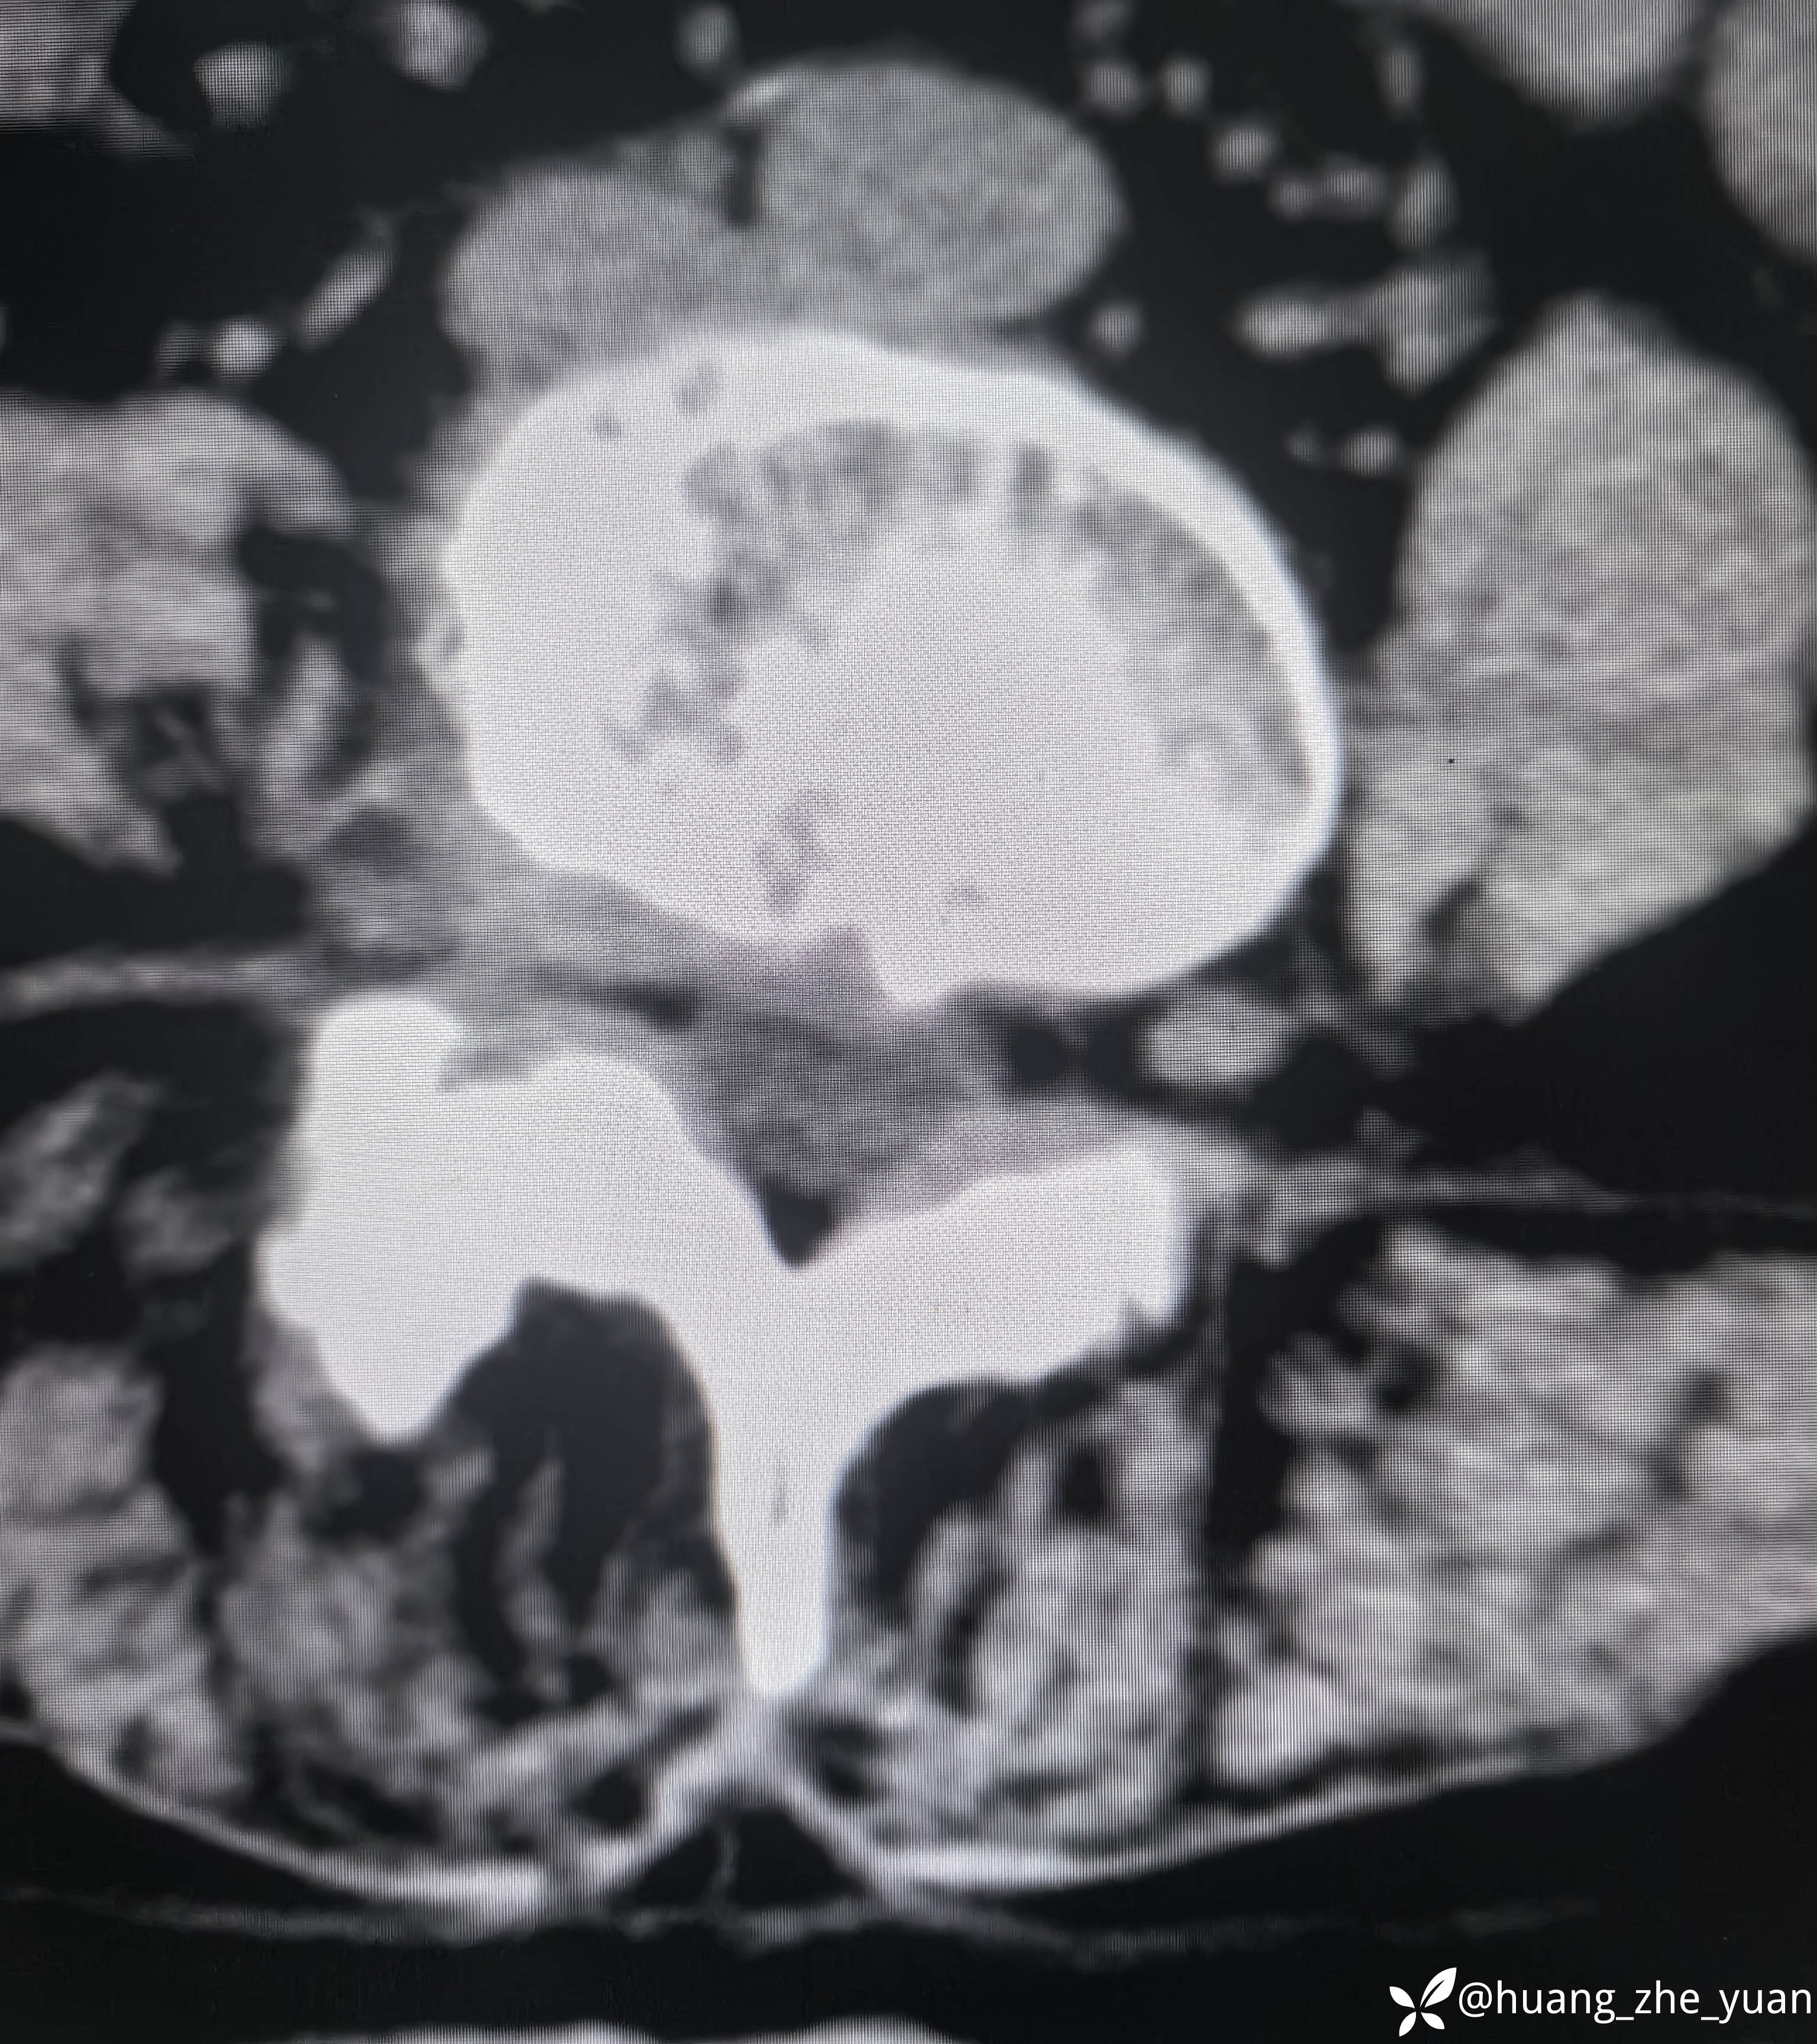

70岁女性,反复右下肢放射痛八个月。合并症:糖尿病,胰岛素泵控制。